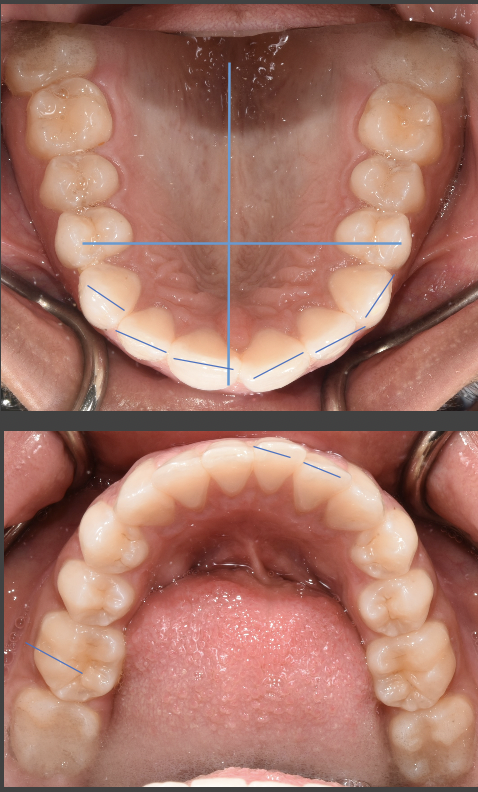

Good Morning, I have had braces for 20 months, but my orthodontist told me I would only need them 3 months! I basically was a relapse case. I had Invisalign in 2007-2008 to close a gap in my front teeth, and a permanent retainer was affixed to the back of my front four teeth to keep the gap closed. My current orthodontist finished my Invisalign case with a Howley retainer and elastics, after I initially had gone to a general dentist to start my Invisalign case. I was very pleased with my smile at the conclusion of my Invisalign case in 2008! In early 2016, my gap re-opened after my permanent retainer broke. It only took around two weeks for the gap to reopen upon the retainer breaking! I went to get the retainer repaired, and the gap had re-opened too wide for my orthodontist to close with finger pressure. Therefore, my orthodontist recommended a Howley retainer to try to remedy the problem. The Howley retainer closed the gap, but the top teeth did not meet well with the bottom teeth, causing malocclusion and 'hitting' of the two rows of teeth. Therefore, traditional metal braces were introduced as a solution. Again, my orthodontist said I would only need 3 months to conclude my braces treatment! It has now been 20 months! My braces treatment started in September 2016. At the three-month mark, I thought my bite was good, and my teeth were looking pretty good. About 5 months into treatment, I noticed there was a space forming in between my two left canine teeth. That caused the left side of my smile not to 'fit' together. It made my smile look uneven. My orthodontist tried to remedy this by making me wear elastics off on and on for over 6 months (between February 2017 - October 2017), but the space did not close as I liked by October 2017. They don't fit together much better now. At this time in October 2017, my orthodontist was talking about doing an impression! As much as I wanted to take my braces off at this time in October, after going 4 times the amount of time I thought I would be in braces (12 months at that time), I knew I would not be pleased with this result. Due to my dissatisfaction, My orthodontist then instituted other elastic configurations to see if this would help, but the desired result still did not happen. I visited other orthodontists for a second opinion on how to close the space better, and they recommended adjusting brackets to put more force on the teeth at better angles to make them fit. I mentioned moving brackets to my orthodontist. However, for some reason, my orthodontist was against moving brackets, always saying "I don't need to do that. I can bend the wire." She insisted that only young orthodontists use the adjusting of brackets as a method, particularly because that is how they were taught, and they aren't familiar with bending wires, as she, an older orthodontist, is familiar. She said that younger orthodontists aren't trained to bend wires now, as she was taught. My orthodontist finally begrudgingly moved the bracket on my top canine higher on the tooth, around early March 2017, after I asked for a third time. I did not want the bracket moved higher, but lower, as I wished to tilt the crown of the tooth more upward. However, my orthodontist did it her way. Her moving the bracket higher caused the top canine to come down in an unsightly fashion, almost at an angle. It also exacerbated the situation, as it made the space between the canines much bigger. It stayed like this over two months inexplicably (this is when I started to get other second opinions), and she just closed the space in late April, with an adjustment. The photo I have posted is how my teeth look now. I wanted to post photos that show change from the beginning until now, but there seems to be one-photo limit on this site. In the current photo, I still don't think my left canines meet well, and the top canine still comes down at a less than aesthetic angle and sort of just overlaps the bottom canine, rather than 'fitting' it. Another issue that makes my smile look uneven is that my left and right incisors are not level with each other. You can see that in the photo. My orthodontist has not been able to successfully address this either. She has tried to use a powerchain to bring the bottom teeth inwards, so the top teeth can come down more, and thus the left incisor can be moved down, but the powerchain has not worked. To sum up, my orthodontist's 'bending of the wires' has not moved my teeth into the desired position. It's really as if there has been hardly any real noticeable movement from February 2017 to now May 2018. I would think from all of that time to perfect, my teeth would look amazing now, but they don't. If you look at my photo, the spaces mentioned above make the left side of my teeth look a little jagged and 'open'. The right side of my smile is well spaced, and 'closed' from the front. What I mean by 'closed' is that you only see white teeth connected, and no spaces or fault lines. However, there are still spaces in between teeth on the left side, namely between the left incisor and the left front tooth at their bases, and the left canines are not meeting flush, but overlapping moreso. I simply want the left side of my smile to match the right side of my smile, particularly from the front. I must note that from my side profile, there are still some fault lines from the side, where teeth don't seem to meet the best way as well. However, I could be willing to deal with this if the teeth can be fit better from the front. My orthodontist doesn't seem to have the ability to move brackets strategically and does not seem flexible enough for me as a patient. It feels like every time I have an appointment, she is just doing trial and error, with no real conclusive plan on how to solve my problem. This has been going on for over a year in regards what I felt were easy problems to solve! I am thinking of changing to an orthodontist whom I consulted for a second opinion, whom uses more advanced techniques than my current orthodontist. I am beyond frustrated and fatigued of wearing braces. I am an older man, at 38 years old, and only agreed to get braces because I was told my initial issues (closing a gap between my two front teeth, and re-positioning my bottom teeth) would only take 3 months to treat, and there were no other issues. My orthodontist has non-urgently taken nearly 8 times that amount of time, only to leave me with dissatisfaction. I would like to go to another orthodontist. However, I don't want to pay out more money if this is an issue that can't be remedied any more than it already has. What do you recommend from looking at my picture? The other orthodontist whom I consulted for a second opinion, recommended wearing 'inside-out' rubber bands to 'tuck' the top-left canine in better and have it meet better with the bottom, and then proceed with bracket adjustment to finish the space closure for a better fit. To allow the left incisor to come down more to be level with the right incisor, they recommended potentially doing interproximal reduction on the lower four teeth to create more room to angle them inwards, which would allow the top row to come down more and look more even with the bottom (so my smile would look more even overall). Thus, the left incisor could be brought down more and and be positioned level with the right one, without malocclusion and hitting on the bottom teeth, which has been a problem as well. She said the interproximal reduction would also allow the top two front teeth to rest better on the bottom teeth and not hit too hard, which would help my gap stay closed better than the current position would. This would help avoid a second relapse. Do you think these methods and suggestions from the second orthodontist could work to fix my issue(s)?